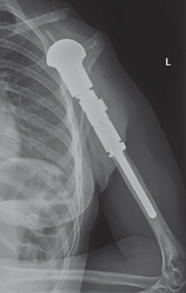

Proximal Humerus Tumor Prosthesis

This prosthesis is sized and built during the surgical procedure then implanted. We cement the prosthesis into your bone and safely secure it in place